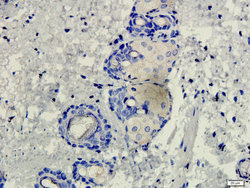

Supportive validation

- Submitted by

- antibodies-online (provider)

- Main image

- Experimental details

- IHC